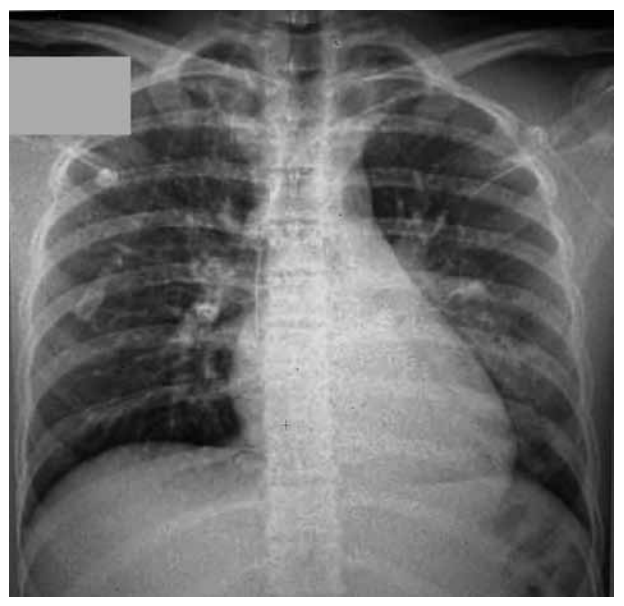

Uma criança de 11 anos deu entrada no pronto-socorro com cefaleia e dor torácica associadas à temperatura de 38,5 ºC.

Clinicamente, apresentava uma ausculta com diminuição do murmúrio vesicular na base esquerda, tempo de enchimento

capilar de 4 segundos e pressão arterial de 90 x 55. Foi puncionado acesso venoso, foram iniciadas expansões volêmicas

de 20 mL/kg por duas vezes no pronto-socorro, e a criança foi encaminhada para a UTI. Foram solicitados exames laboratoriais e raio-X de tórax (figura a seguir). Na entrada na UTI, constatou-se PA igual a 66 x 40.

(Arquivo pessoal; imagem usada com autorização)